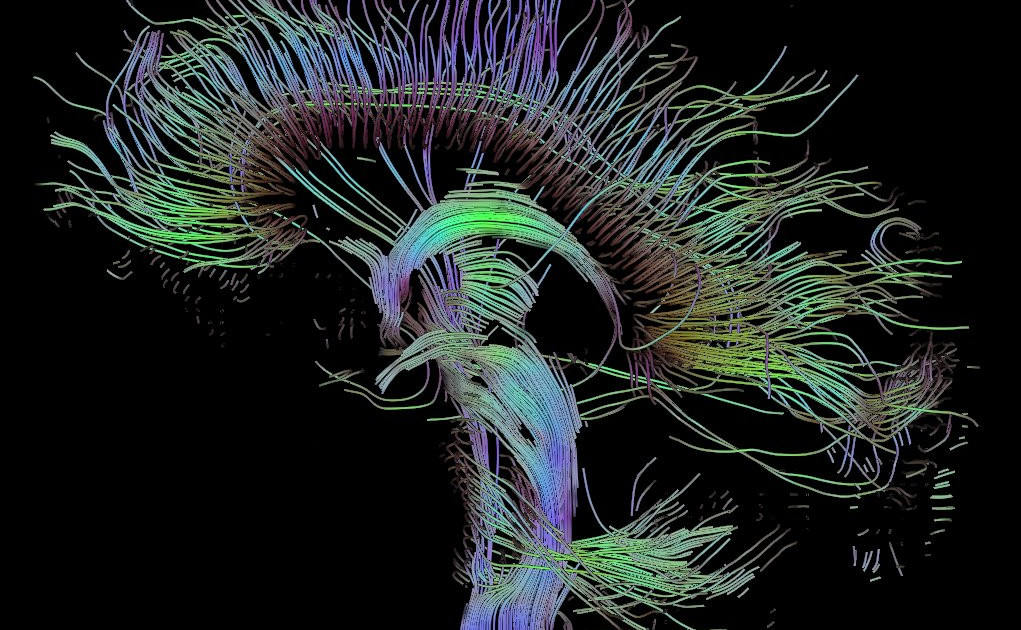

Zemljevid delovanja možganske aktivnosti imenujemo konektom. Konektom si lahko popreproščeno predstavljamo kot mrežo, v kateri so podrobno predstavljena različna možganska omrežja, njihovo delovanje in moč povezav med njimi. Podobno, kot ima vsak izmed nas unikaten prstni odtis, je unikaten tudi konektom posameznika. Izdelamo ga na podlagi kopice magnetnoresonančnih slik, ki posredno prikazujejo možgansko aktivnost z zaznavanjem povišanega pretoka krvi v aktivnejših možganskih predelih.

****izvor in licenciranje uporabljene slike:

This file is licensed under the Creative Commons Attribution-Share Alike 3.0 Unported license.

Rendering is own work, using a modified version of the BioTensor application developed at the University of Utah. The dataset is courtesy of Gordon Kindlmann at the Scientific Computing and Imaging Institute, University of Utah, and Andrew Alexander, W.M. Keck Laboratory for Functional Brain Imaging and Behaviour, University of Wisconsin, Madison. It is publicly available. Author: Thomas Schultz